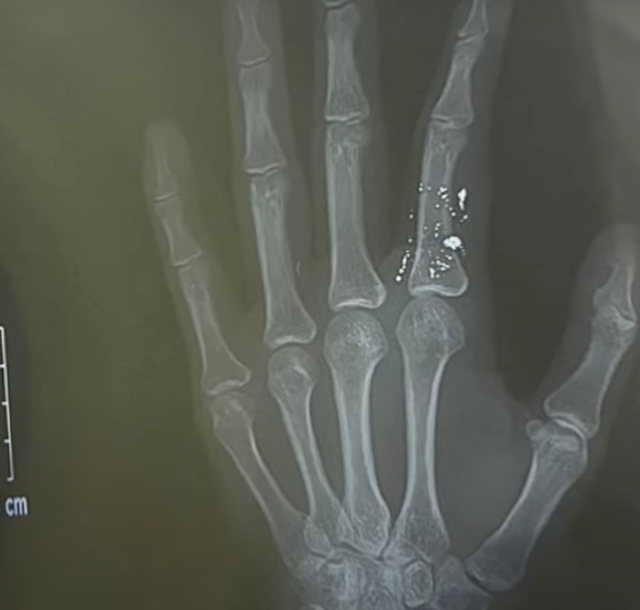

Kết quả quả chụp X-quang cho thấy hình ảnh ngón 2 bàn tay trái chứa nhiều hạt thủy ngân. Bệnh nhân được chuyển lên tuyến trên theo dõi, điều trị.

Bác sĩ Nguyễn Mạnh Chiến, Trung tâm chống độc, Bệnh viện Bạch Mai, cho biết tại đây bệnh nhân được chẩn đoán bị nhiễm độc thủy ngân với tình trạng ngón 2 bàn tay trái sưng nề, đồng thời trên phim chụp có rất nhiều hạt thủy ngân ở ngón tay chưa thoát được ra ngoài.

Bệnh nhân được điều trị kháng sinh và phẫu thuật gắp toàn bộ hạt thủy ngân trong ngón tay bởi các bác sĩ chuyên khoa phẫu thuật tạo hình thẩm mỹ của bệnh viện. Sau ca phẫu thuật, ngón tay của bệnh nhân hiện không còn chứa các hạt thủy ngân, tay người bệnh đã đỡ đau hơn.